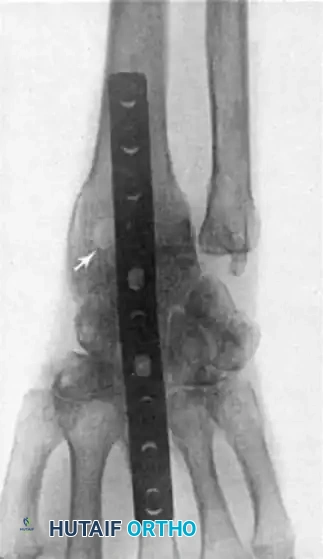

If the DRUJ remains unstable after soft tissue repair, temporary transarticular K-wire fixation may be necessary to protect the repair during the initial healing phase.

Radiographic confirmation of temporary transarticular K-wire fixation stabilizing the DRUJ following complex TFCC repair.